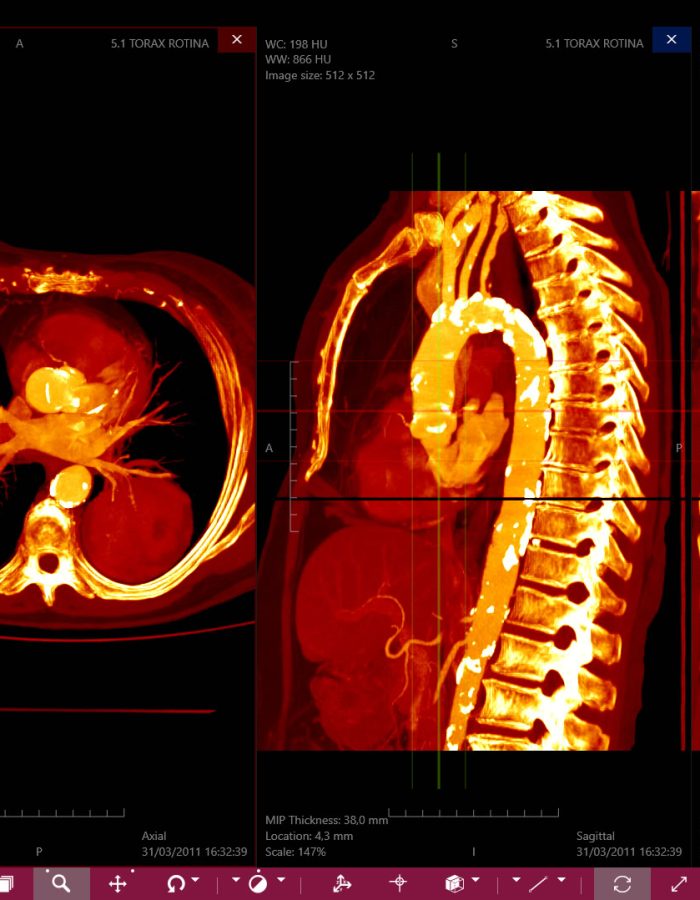

_ Amplia variedad de imágenes con un estilo profesional, tanto para estudios de casos pre operatorios como para estudio profundo de medicina.